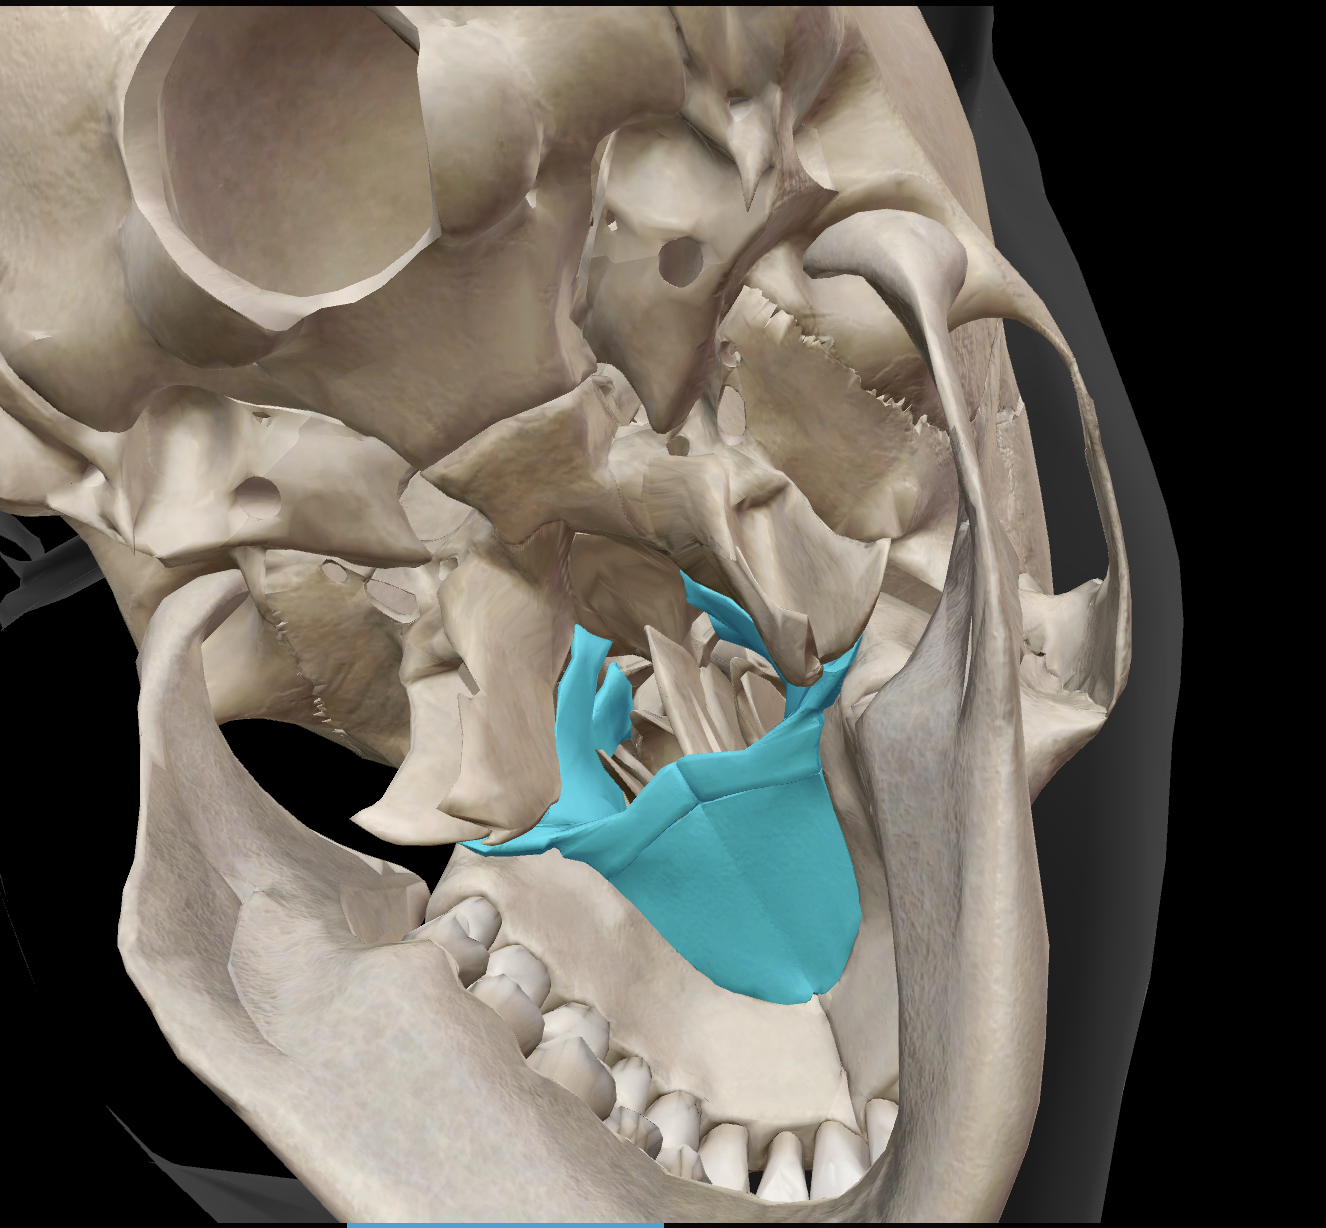

What is the name of this feature?

superior orbital fissure

What is the name of this feature?

zygomatic process of temporal bone

What is the name of this feature?

external auditory meatus

What is the name of this feature?

mandibular fossa